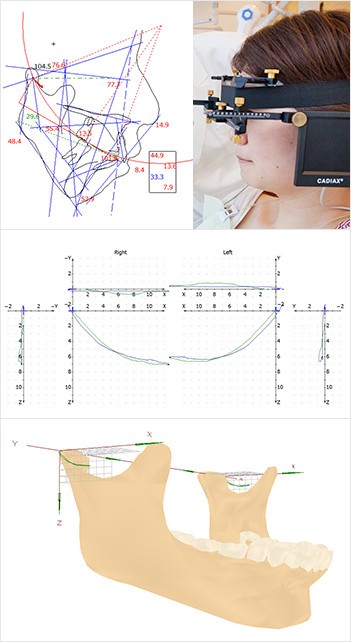

ウィーン大学名誉教授R.Slavicek(R.スラヴィチェック)博士の理論に基づいた顎機能咬合診断診療プログラムを導入しています。特に顎関節症に有効な診査・診療プログラムとされ、矯正治療の前の検査で使われます。キャディアックスは、このプログラムの中で使うキャディアックス下顎運動測定装置とデータ解析プログラムのことで、これまでの検査では測定できなかった顎の動きをグラフや動画で明らかにすることがでます。キャディアックス下顎運動測定装置により得た下顎の動きの範囲や角度などのデータを解析することで、患者様の持つ個々の骨格形態や噛み合わせを科学的に分析し、顎関節症の治療や矯正治療などを行うための包括的治療に役立てることができます。

キャディアックスは以下の診療に使うことができます。

顎関節症

これまで困難だった顎の動きを測定できるようになったため、CTや模型データと統合した、より科学的な分析が可能です。患者様一人ひとりの最適な顎の位置、形状、歯列や噛み合わせ等を算出し、その理想値と実際の測定値を照らし合わせる事で、負担のかかる患部、原因、予測されるリスクや症状の深刻さを検討したうえで、的確な治療計画を提示し、包括的かつ根本的な顎関節症治療を実現します。

矯正治療

歯並びが悪く、噛み合わせが合わないまま噛み続けていると顎に負担がかかり、顎関節症にかかるリスクが高まります。矯正治療では、歯並びを整えるだけでなく、キャディアックスにより正しい顎の位置を割り出して「正しい噛み合わせに導く」というゴールにむけて治療していきます。